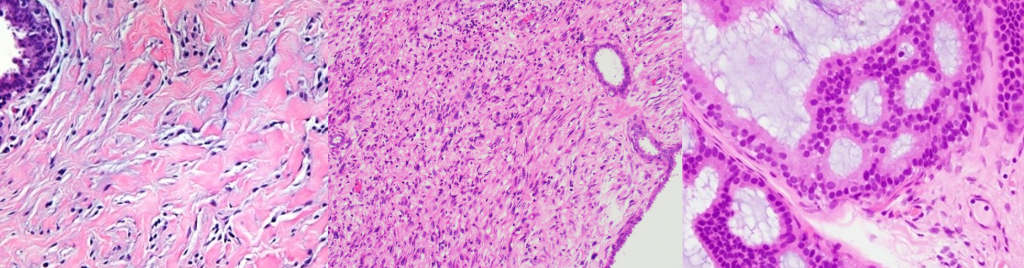

The Division of Women’s Health Pathology at the University of Alabama (UAB) Medical Center, Birmingham, offers a one-year Fellowship/Instructorship position in Diagnostic Breast Pathology with advanced comprehensive training experience, graduated responsibilities, and sign out privileges. With the high level of complexity of breast pathology cases, and the leading role of Breast Pathologist in multidisciplinary management team, breast pathology has become a highly desirable area. The Breast Pathology Section at UAB provides diagnostic interpretations of routine screening breast pathology and Breast oncology specimens for UAB Hospital, satellite clinics, and O'Neal Comprehensive Cancer Center patients. It receives consultations that serve UAB Pathology outreach services (CPPP), other local and regional institutions, providing comprehensive review of the cases. From the approximately 60,000 surgical pathology accessions performed at UAB Surgical Pathology laboratory, about 4000 represent breast pathology specimens, including in-house biopsy and resection specimens and consultation material. Fellows are expected to present monthly Rad-Path conference and to attend weekly Tumor Board conferences based on schedule and supervise residents in the gross room. In addition, fellows have a chance to rotate in Breast Imaging. Fellows are encouraged to participate in ongoing basic or translational research projects in collaboration with the Breast Pathology section faculty members, leading to publications and presentations at national meetings. The program is optimized with structured didactic lectures and slide sessions relevant to daily practice. Rotations take place at The University of Alabama Hospital. Combined Breast/GYN or Breast with another subspecialty fellowship options are also available.